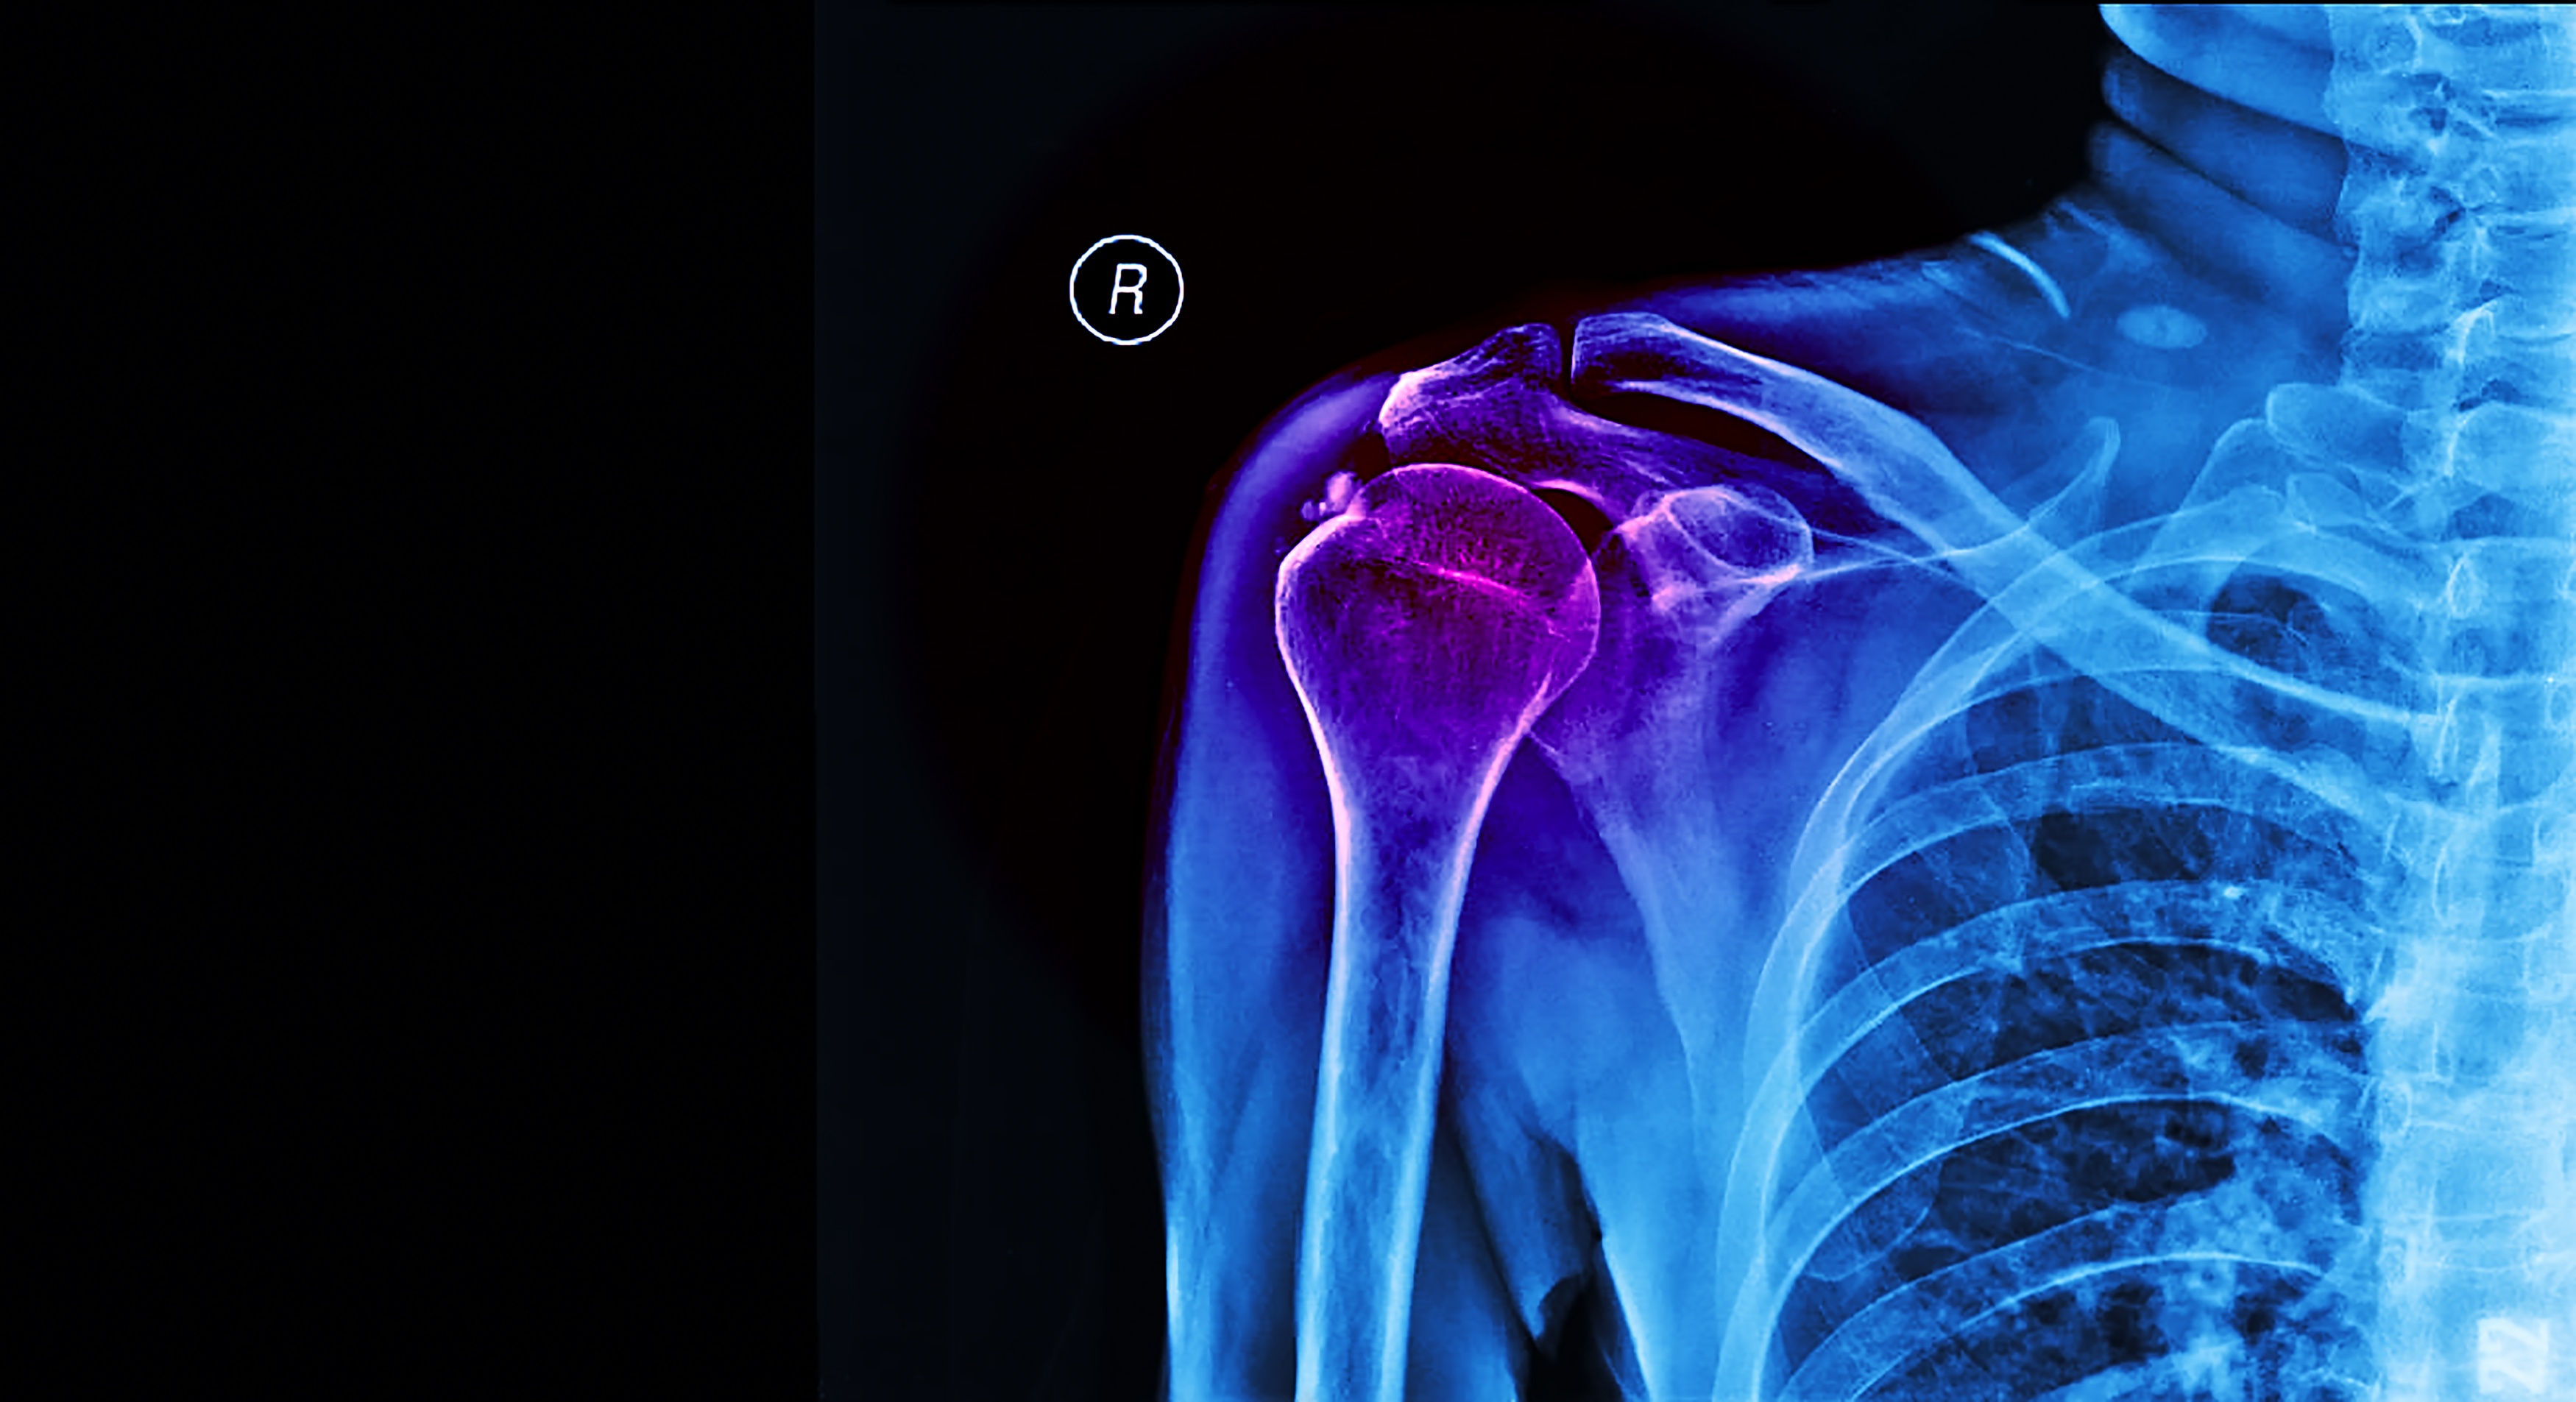

New Approaches to Knee and Shoulder Arthroplasty .

Advances in knee and shoulder arthroplasty are reshaping how surgeons approach joint reconstruction and implant design. Emerging strategies emphasize personalized alignment, improved implant kinematics, and technologies that enhance surgical precision. In knee arthroplasty, innovations such as kinematic alignment philosophies, patient-specific instrumentation, and robotic-assisted techniques aim to better replicate native joint mechanics and improve functional outcomes. Meanwhile, shoulder arthroplasty continues to evolve with expanded indications for reverse shoulder implants, improved glenoid fixation, and refined implant geometries designed to enhance stability and longevity. Together, these developments reflect a broader shift toward more individualized joint replacement strategies—combining advanced implants, data-driven planning, and surgical technologies to optimize patient outcomes and durability of reconstruction.